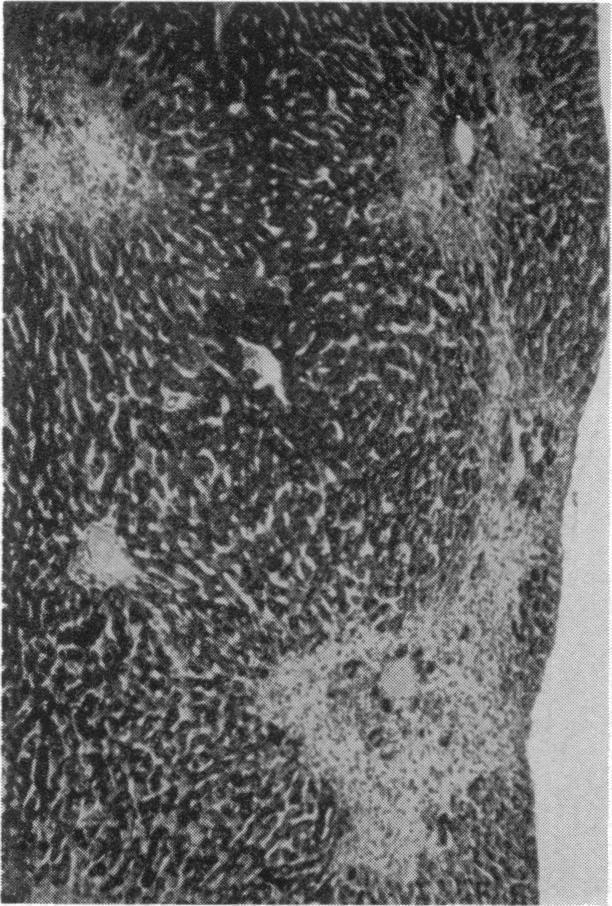

Case of Mesenteric Reticulosarcoma Associated with Gluten-sensitive Steatorrhoea.

Br Med J. 1961 Aug 19;2(5250):496-480.2. doi: 10.1136/bmj.2.5250.496.